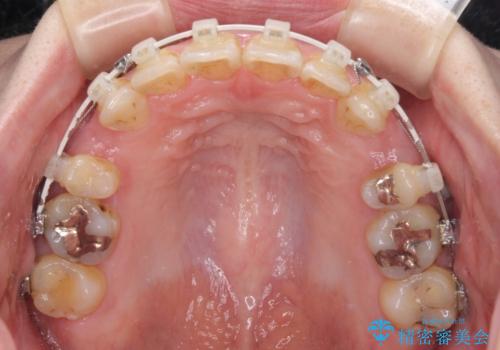

- 矯正装置

- 審美装置

上下前歯の距離が大きかったため、上下の歯が接触するまでに時間がかかりました。

それでも目安である2年半で終えることができ、患者様には大変満足していただけました。